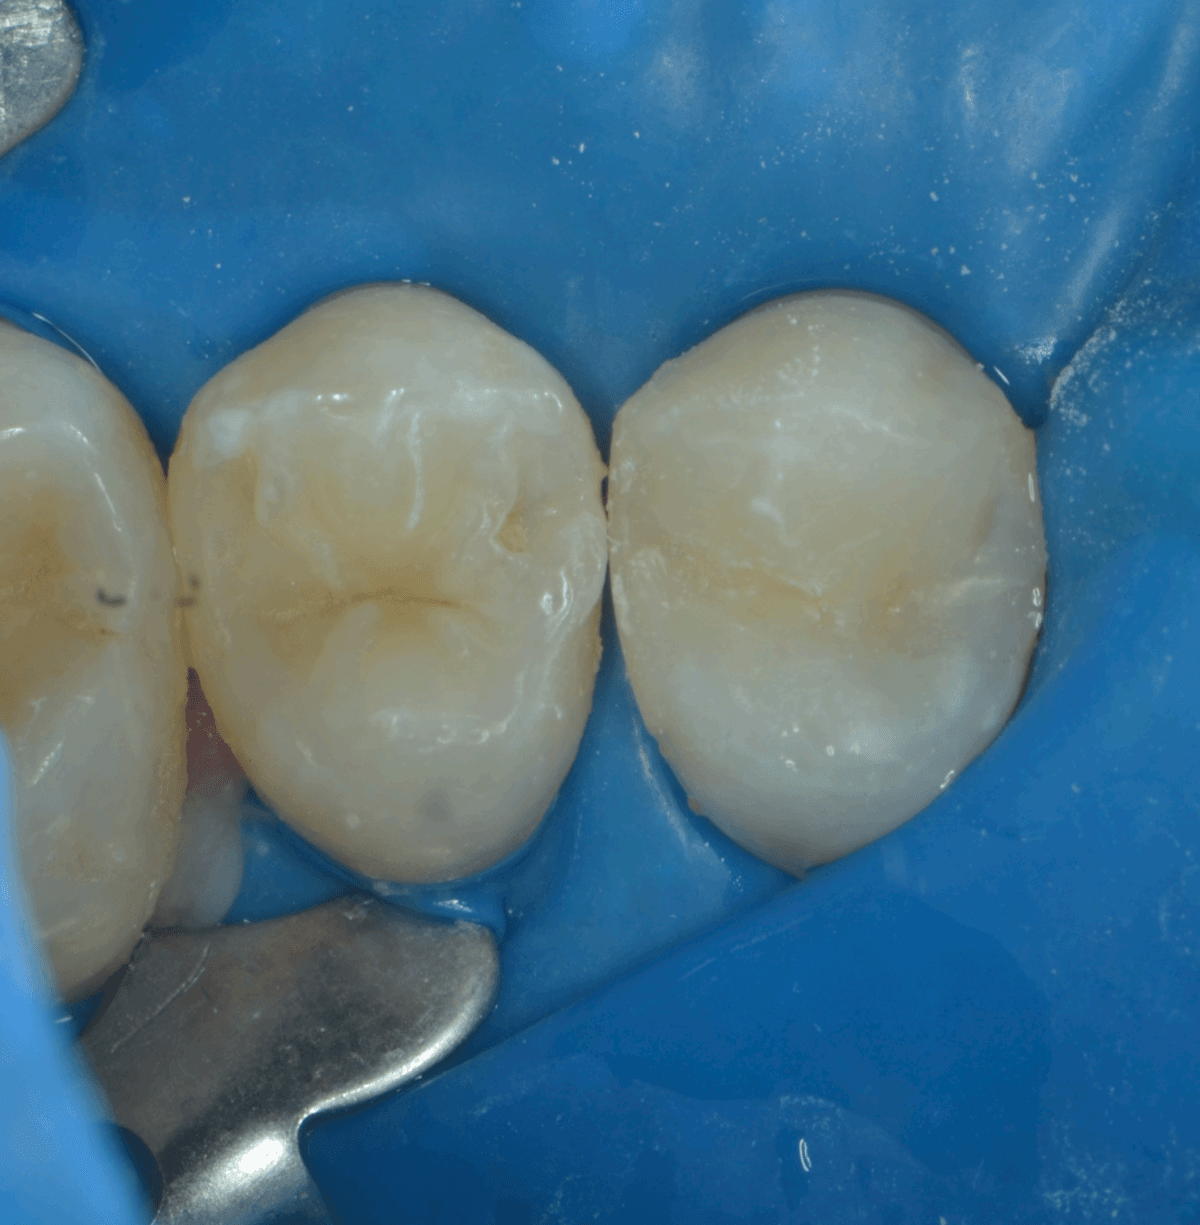

La clinica stomatologică MB Dental din Târgu Mureș, tratăm fiecare carie cu precizie, utilizând microscopul dentar pentru a identifica și elimina complet țesuturile afectate. În acest caz, pacientul s-a prezentat cu o carie interdentară localizată între premolarii superiori, o zonă dificil de accesat și frecvent afectată de acumularea resturilor alimentare.

1. Diagnosticarea cariei: Utilizând microscopul dentar, am identificat o carie ascunsă între premolarii superiori. Această zonă este predispusă la formarea cariilor din cauza dificultății de curățare și a acumulării de resturi alimentare.

2. Îndepărtarea țesutului cariat: Am eliminat cu atenție țesutul afectat, păstrând cât mai mult din structura sănătoasă a dintelui.

3. Reconstrucția dintelui: Am realizat o obturatie dentară stratificată, aplicând compozitul în layere fine pentru a asigura o adaptare perfectă și o estetică naturală.

4. Finalizarea tratamentului: După finisarea și lustruirea obturației, am verificat ocluzia pentru a asigura confortul pacientului.